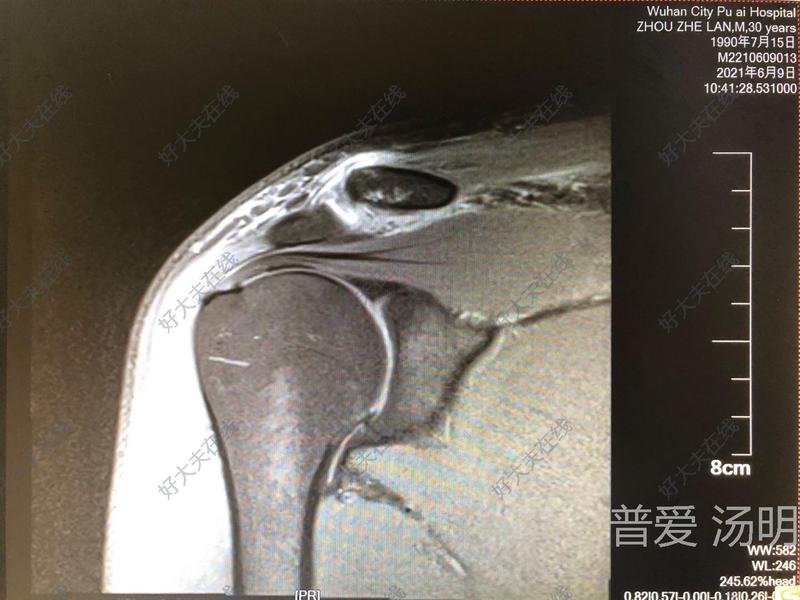

肩锁关节脱位

汤明医生的科普号